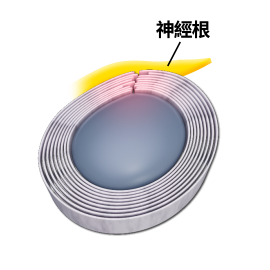

「頸源性頭暈」便是指疾病是與頸部問題最為相關。頸是連接頭部與軀幹的橋樑,它包含脊椎、血管 和神經組織(Fig.1),對活動和生存至關重要,任何傷害這條橋樑或這條橋樑出現病患,對維持人體健康或身體機能有關鍵影響。

(1)上頸椎神經受壓:

因為頸椎分為上頸椎和下頸椎,頸椎C3節為分介線,C3以上椎節為上頸椎節,C3以下椎節為下頸椎節。凡是上頸椎神經受壓,例如:椎間盤突出、椎孔狹窄、椎體移位或下陷,都會有機會導致前額痛、後枕痛、眼窩痛、上頸椎痛。